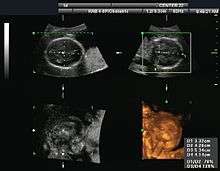

| Obstetrics | Obstetrical sonography is commonly used during pregnancy to check on the development of the fetus. | see obstetric ultrasonography |

3D images can be generated by acquiring a series of adjacent 2D images. Commonly a specialised probe that mechanically scans a conventional 2D-image transducer is used. However, since the mechanical scanning is slow, it is difficult to make 3D images of moving tissues. Recently, 2D phased array transducers that can sweep the beam in 3D have been developed. These can image faster and can even be used to make live 3D images of a beating heart.

Obstetric ultrasound

Obstetric ultrasound can be used to identify many conditions that would be harmful to the mother and the baby. Many health care professionals consider the risk of leaving these conditions undiagnosed to be much greater than the very small risk, if any, associated with undergoing an ultrasound scan.

Sonography is used routinely in obstetric appointments during pregnancy, but the FDA discourages its use for non-medical purposes such as fetal keepsake videos and photos, even though it is the same technology used in hospitals.[63]

Obstetric ultrasound is primarily used to:

- Date the pregnancy (gestational age)

- Confirm fetal viability

- Determine location of fetus, intrauterine vs ectopic

- Check the location of the placenta in relation to the cervix

- Check for the number of fetuses (multiple pregnancy)

- Check for major physical abnormalities.

- Assess fetal growth (for evidence of intrauterine growth restriction (IUGR))

- Check for fetal movement and heartbeat.

- Determine the sex of the baby

Its results are occasionally incorrect, producing a false positive (the Cochrane Collaboration is a relevant effort to improve the reliability of health care trials). False detection may result in patients being warned of birth defects when no such defect exists. Sex determination is only accurate after 12 weeks gestation. When balancing risk and reward, there are recommendations to avoid the use of routine ultrasound for low risk pregnancies. In many countries ultrasound is used routinely in the management of all pregnancies.